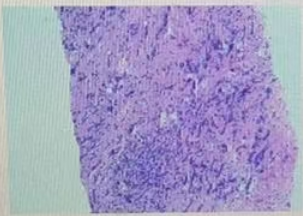

·乳腺钼靶

1、双乳腺体密度混合型ACR c型;

2、双乳小叶增生伴瘤化;右乳外上象限多发结节,考虑BIRADS 4B类,建议进一步MR检查。

图2乳腺DR结果